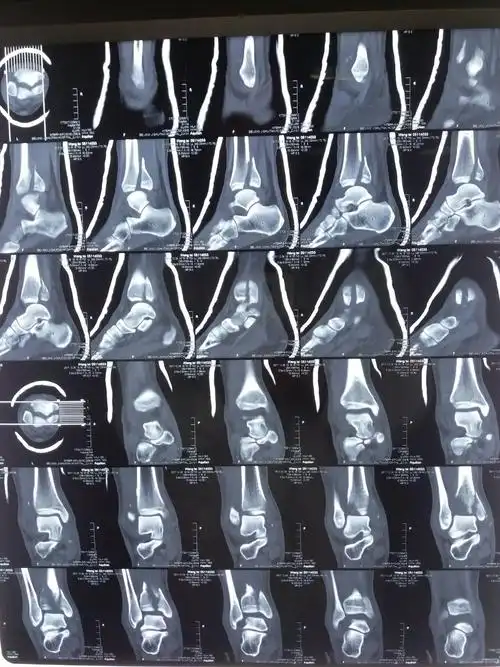

踝关节骨折病例